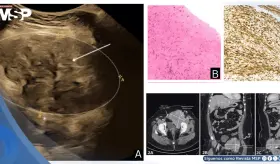

Se confirmó un embarazo intrahepático de 23 semanas, una condición ext...

El caso evidencia los retos diagnósticos que surgen cuando una neoplasia rara coincide con los cambios fisiológicos del embarazo, así como la complejidad terapéutica que implica equilibrar la seguridad materno-fetal frente a las limitaciones de recursos.